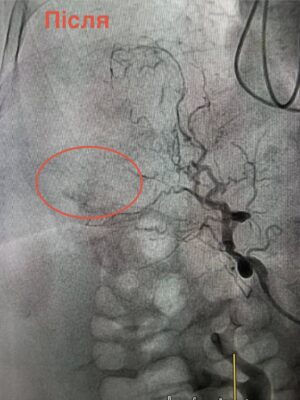

Через загрозливий стан проводити відкриту операцію було неможливо. Натомість лікарі застосували метод ендоваскулярної хірургії — за допомогою ангіографії визначили джерело кровотечі та виконали емболізацію судини, що дозволило її зупинити без масштабного хірургічного втручання.

Завдяки злагодженій роботі команди лікарів жінку вдалося врятувати. До проведення втручання також долучилися фахівці медоб’єднання — Віктор Сало та Тарас Федоришин.